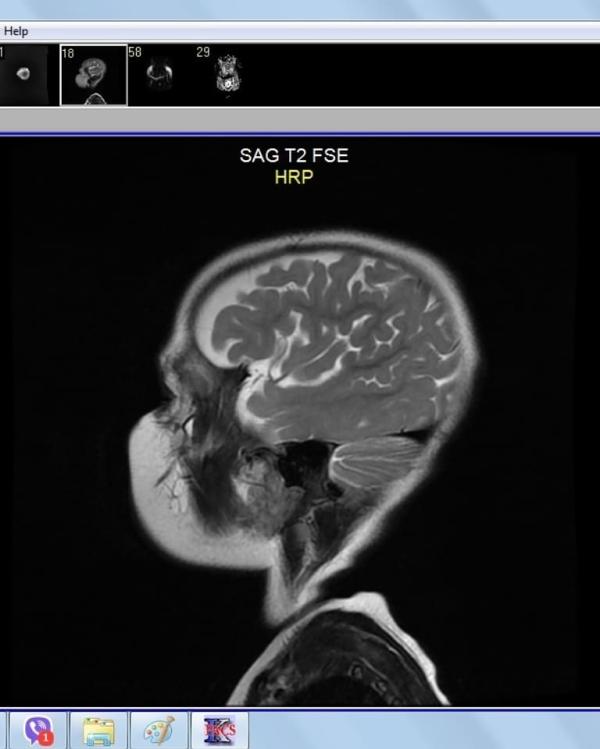

Итак, Соне 1,5 года. У нас уже поставлены диагнозы: ДЦП, двойная гемиплегия, эпилепсия и чазн.

И с этого момента начались наши поездки в Москву. Первым делом, мы поехали на Видео-ЭЭГ мониторинг (ВЭМ). В клинику св. Луки. Там нам подтвердили эпилепсию, добавили ещё один препарат. Поездки стали регулярными, каждые 3-4 месяца, чтоб смотреть динамику. Улучшений не было. Вообще. Были ежедневные приступы, по 10 приступов за день.

В это же время мы делаем МРТ в рдкб. Почему...